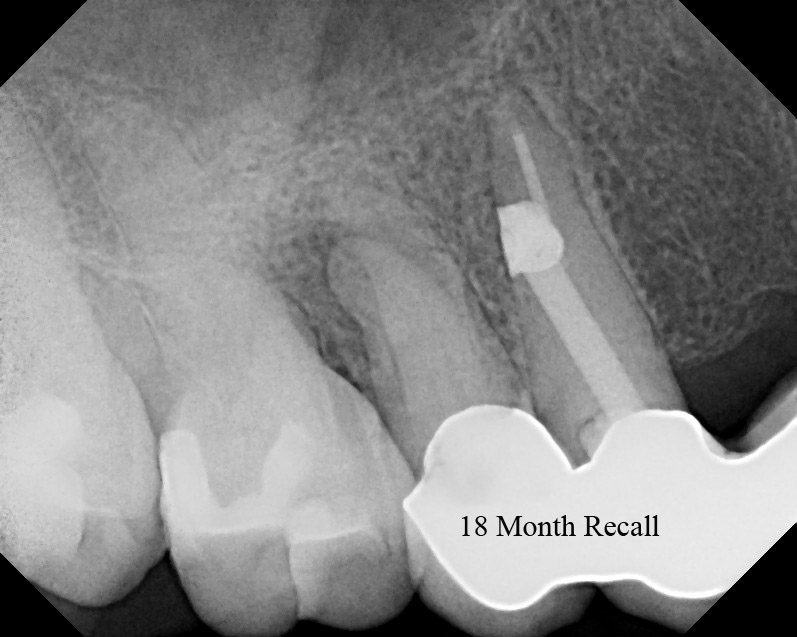

From www.theendoblog.com

The Endo Blog Root Canal Surgery to Repair Post Perforation How To Treat Perforation In Rct Explains the aetiology of root perforations. Regardless of etiology, a perforation should be repaired as soon as possible to discourage further loss of attachment and prevent sulcular. Perforation can be of two types, one that results from a resorptive process and the other, that is iatrogenically produced, which can occur during access cavity preparation and location of canal orifices or. How To Treat Perforation In Rct.